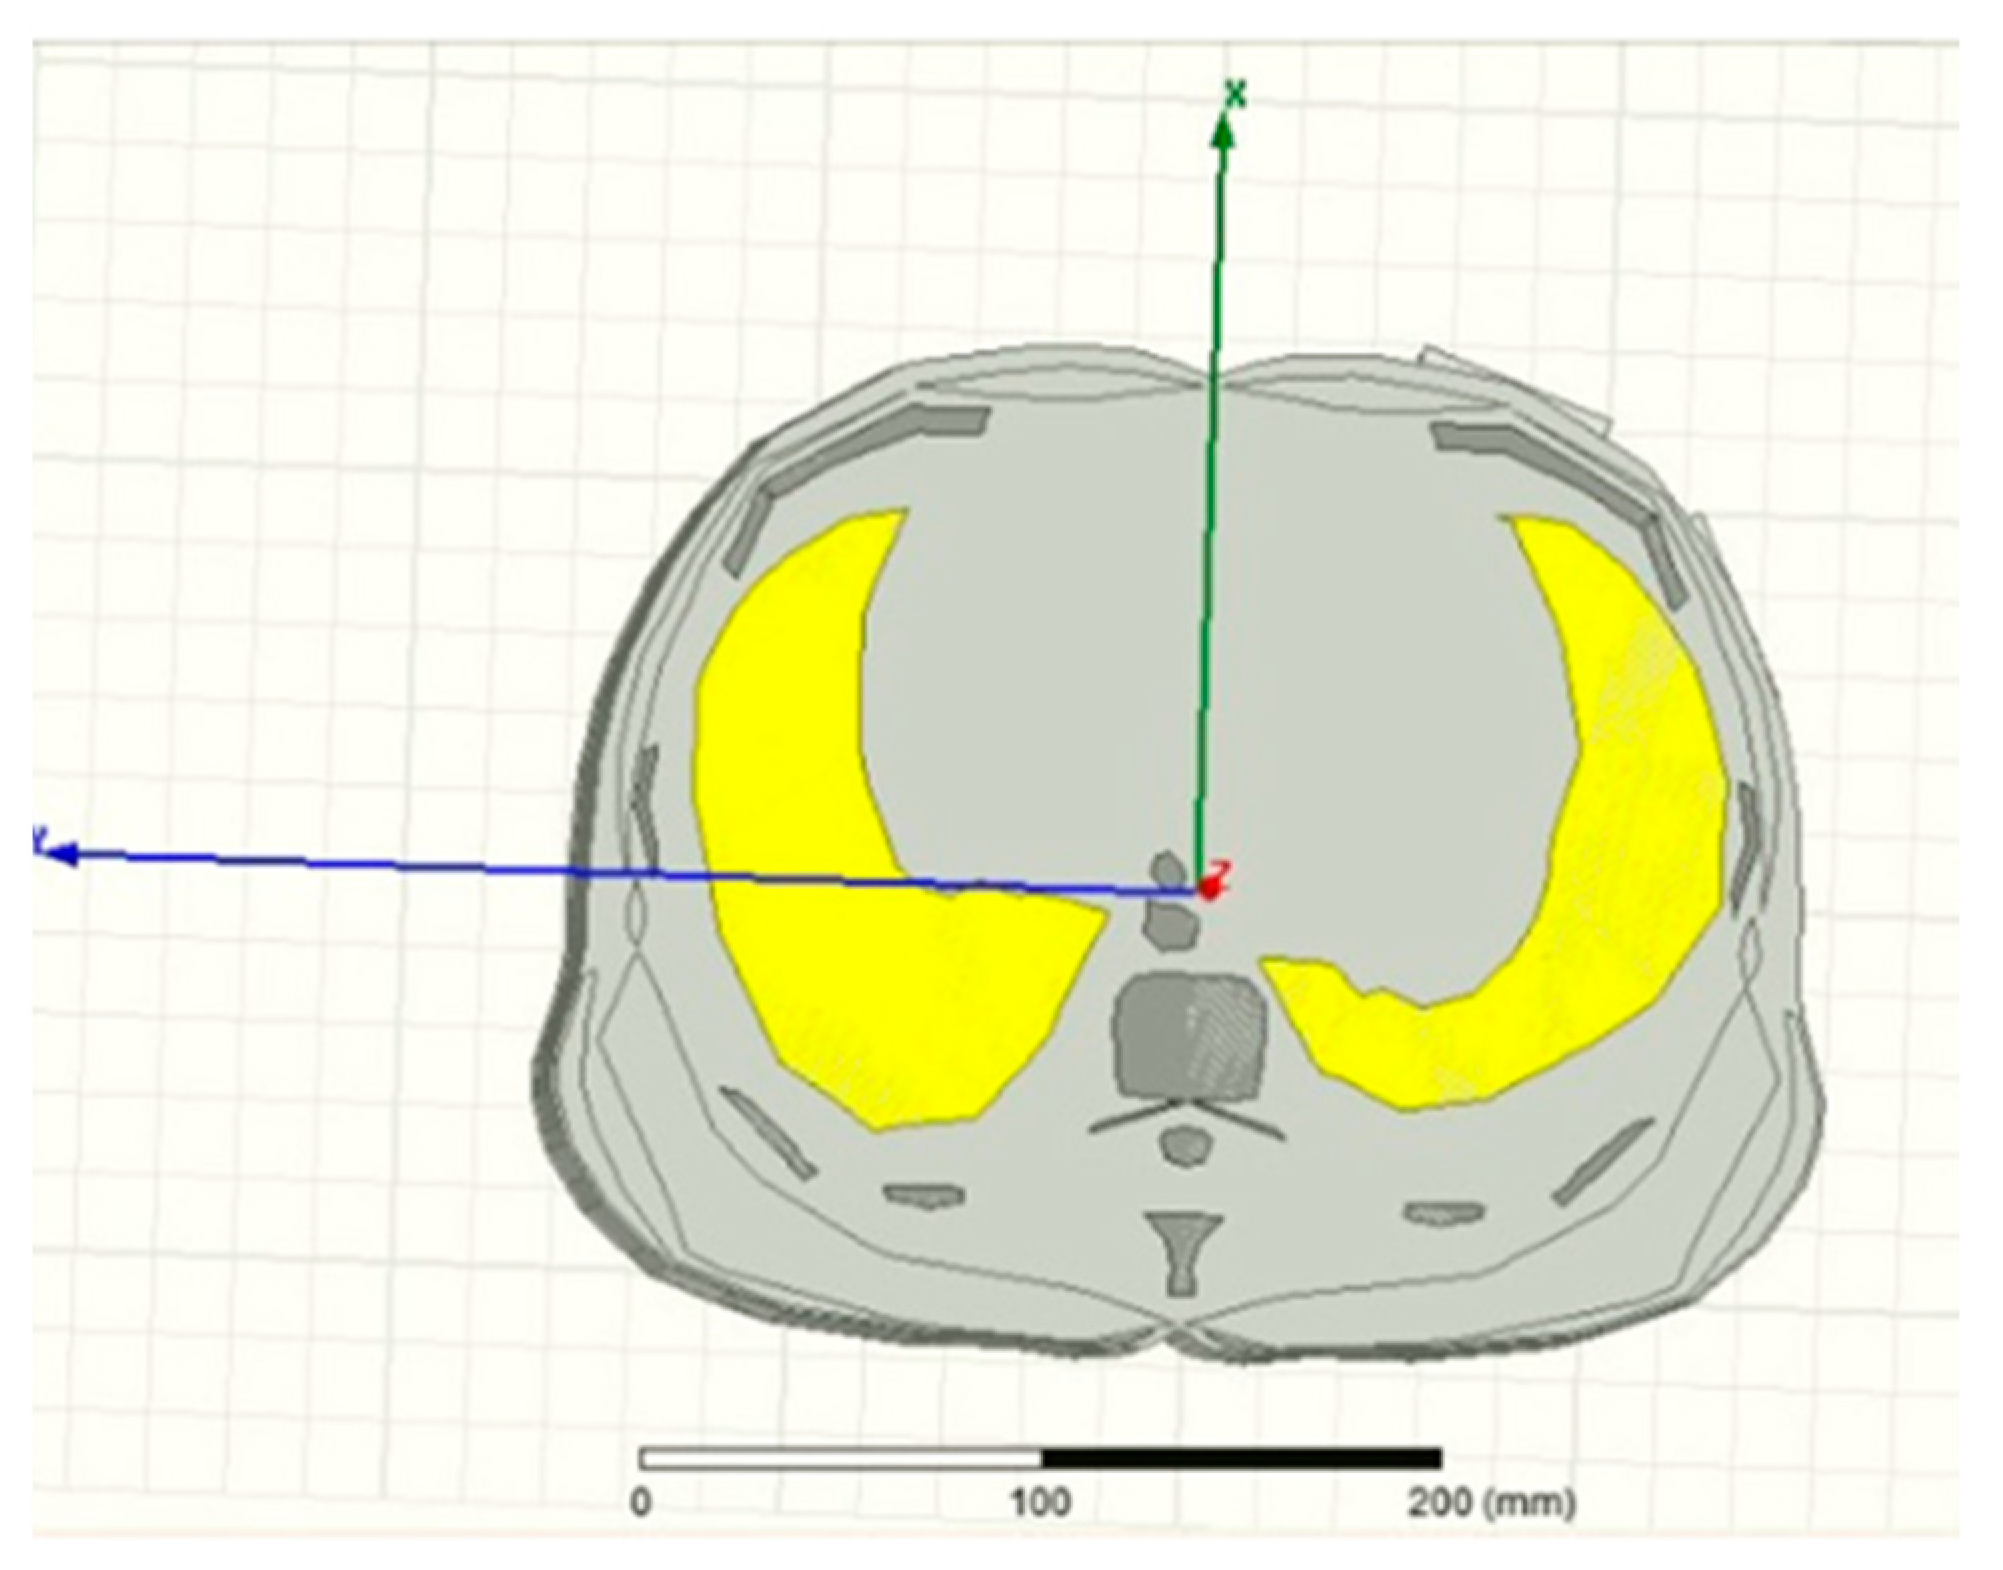

- Leong, C.; Xiao, Z.; Yun, Z.; Iskander, M.F.I. Non-Invasive assessment of lung water content using chest patch RF sensors: A computer study using NIH patients CT scan database and AI classification algorithms. IEEE Access 2023, 11, 13058–13066. [Google Scholar] [CrossRef]